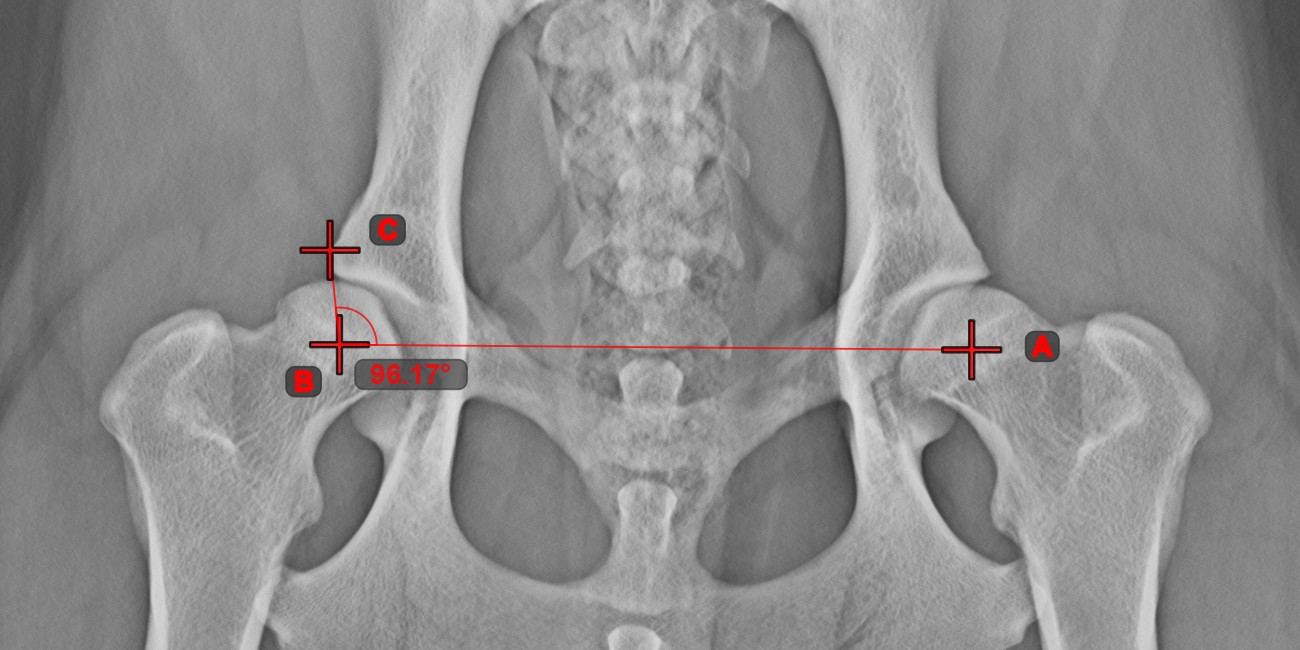

Angle from 3 Points

The Angle from 3 Points tool is a simple and effective way to calculate an angle from just three points.

Start by selecting the tool from the left toolbar and assign it to one of the available mouse buttons. Place the start point of the initial side, the vertex, and the end point of the terminal side of the angle, or select the points from the scene. The sides of the angle will be automatically constructed, thus calculating the angle between the lines.

Modify the position of the three points to change the arc of the angle by using the Select/Move Item tool.

../_images/image56.jpg